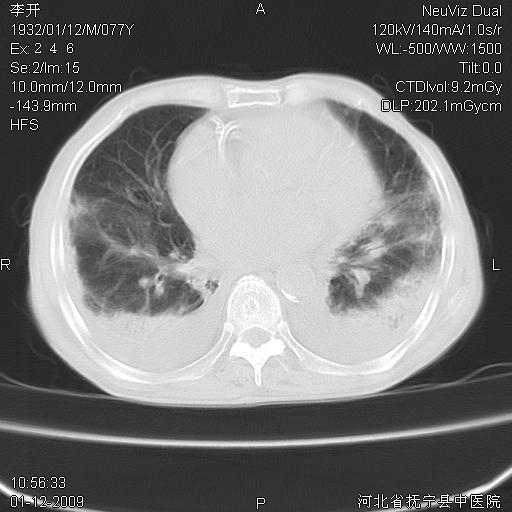

以下是引用黑白光影在2009-1-19 16:49:00的发言:[br]心衰肺水肿;心包、胸腔积液;冠脉钙化;肺部感染。